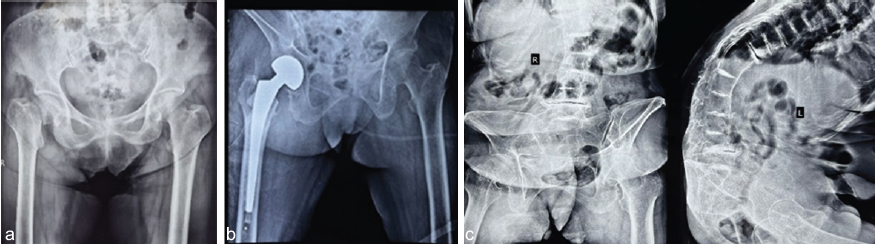

A 75-year-old female presented to the emergency department with an alleged history of a slip and fall, sustaining injuries to the right hip and right wrist. Radiographic evaluation of the right hip revealed a transcervical femur fracture, and imaging of the right wrist showed an extra-articular distal radius fracture (Fig. 1).

Figure 1: (a) Pre-operative X-ray showing right transcervical neck of femur fracture. (b) Post-operative X-ray showing right cemented bipolar hemiarthroplasty. (c) X-ray of spine suggestive of intervertebral disk calcification and degenerative changes.

The patient reported walking with a stooped posture for the past 15 years. She also had a family history of her parents walking with a stooped posture. Radiographic evaluation of the spine demonstrated calcification of intervertebral disks and degenerative changes, resulting in severe angular kyphotic deformity (Fig. 2).